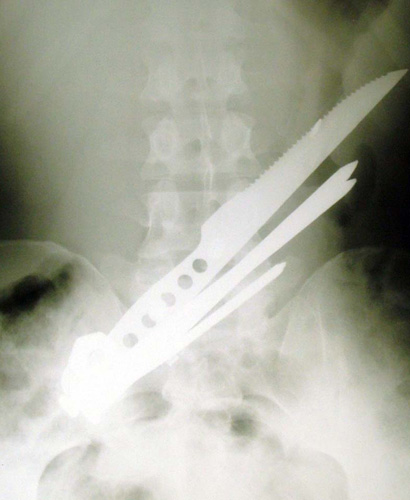

UNNNGH!!

A drunk man had to be rushed to hospital after trying to perform a sword swallowing routine.

(Hold muh beer Unnngh!)

Javlin Magnet!

Unnngh! That's gotta hurt!

When trash picking goes bad?